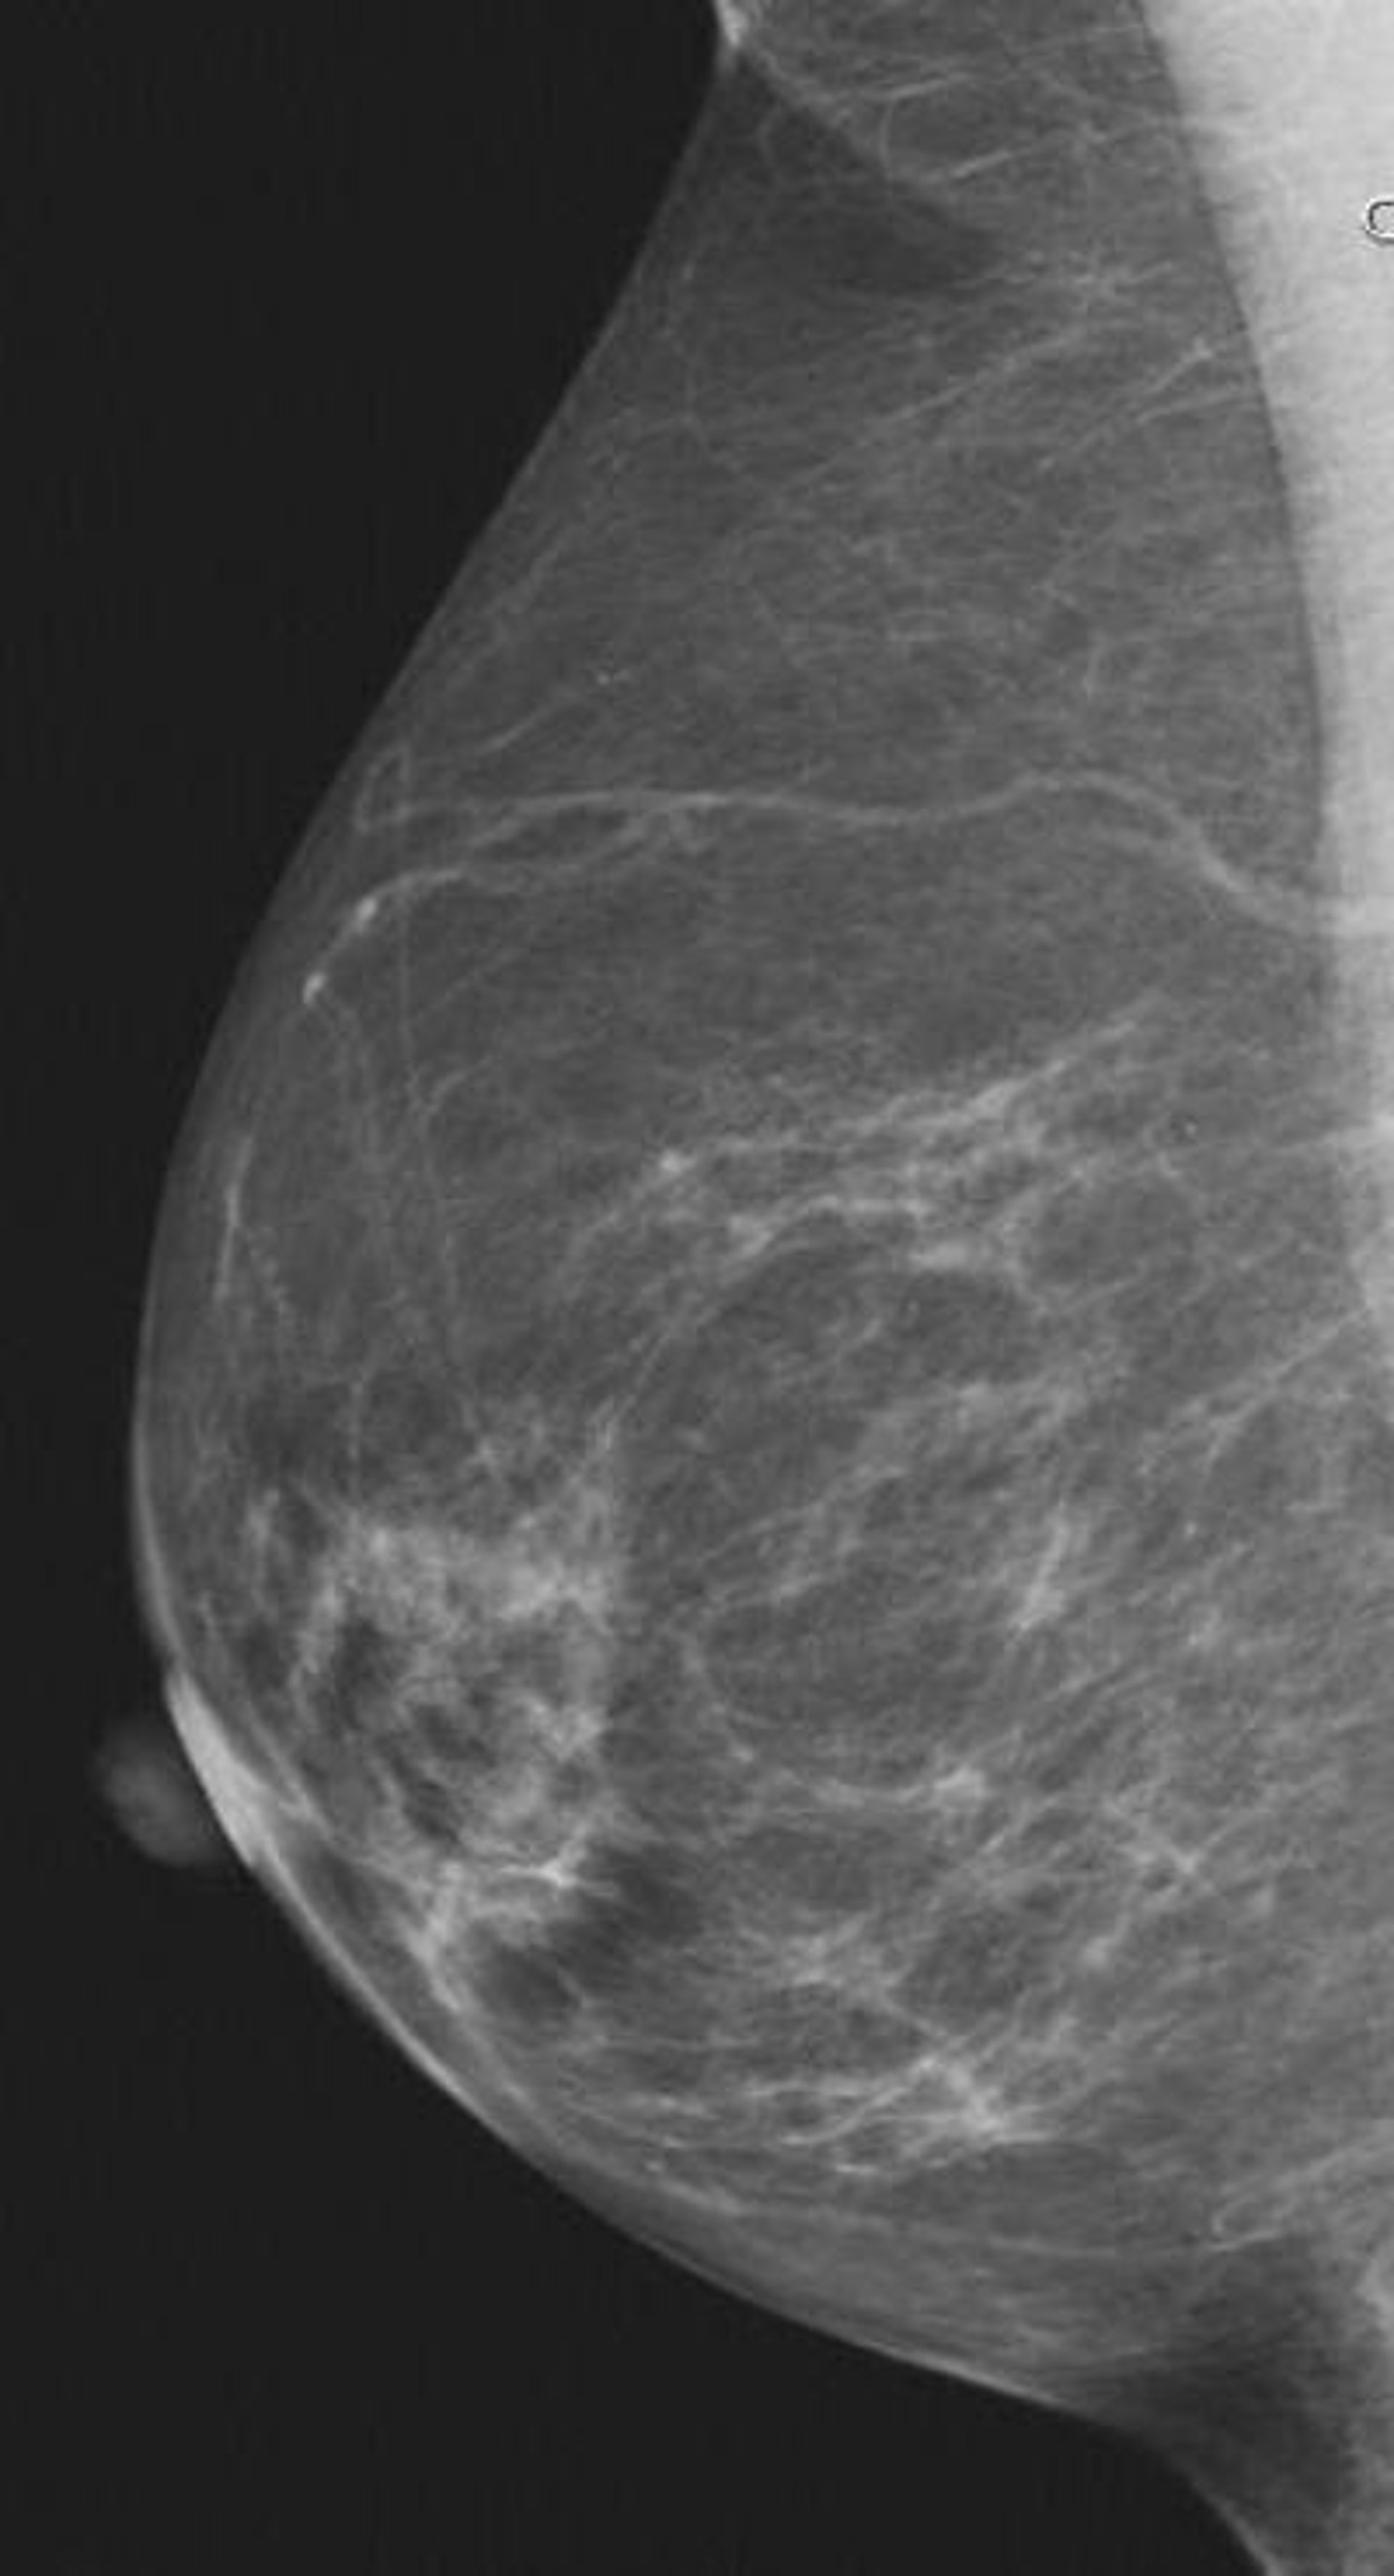

El uso del tratamiento de la diabetes, ya sea por dieta o pastillas como la metformina, disminuye la densidad mamaria (MD, por sus siglas en inglés), uno de los mayores factores de riesgo para el cáncer de mama, mientras que el tratamiento con insulina parece aumentarla, según revela un nuevo análisis que se presenta este miércoles en la 10ª Conferencia Europea sobre Cáncer (ECCO, por sus siglas en inglés).

Aunque estudios anteriores han relacionado la diabetes a la MD, este trabajo se ha centrado en los datos sobre tratamientos para la diabetes y el uso de insulina. La doctora Zorana Jovanovic Andersen, profesora asociada de Epidemiología de la Universidad del Sur de Dinamarca, en Esbjerg, Dinamarca, informa en ECCO de los resultados de un estudio de 5.644 mujeres (4.500 de las cuales eran posmenopáusicas) que fueron reclutadas del estudio 'Danish Diet, Cancer and Health' (DCH) y que se sometieron a mamografías entre 1993 y 2001.

El grupo tenía una edad (promedio) media de 56 años; 137 (2,4 por ciento) padecían diabetes y 3.180 (56,3 por ciento) poseían pechos categorizados como senos densos o mixtos. "Las mujeres con diabetes registraban menos probabilidades de tener senos densos o mixtos, en contraposición a los grasos, tanto antes como después del ajuste por otros factores como el sobrepeso", señala Andersen.

Se hallaron asociaciones inversas similares en las 44 mujeres que controlaban la diabetes mediante la dieta por sí sola, frente a las 62 que tomaban medicación oral para la enfermedad. No obstante, las mujeres diabéticas que usaban inyecciones de insulina poseían mayor probabilidad de tener senos densos o mixtos. Estas asociaciones no se modificaron por el estado menopáusico o por el índice de masa corporal (IMC).

La densidad de la mama es uno de los mayores factores de riesgo para el cáncer de mama, las mujeres con senos de alta densidad (densidad más del 75 por ciento) tienen entre cuatro a seis veces más riesgo que las mujeres con un MD de menos del 25 por ciento.